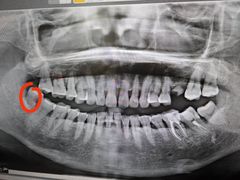

• 爱尚大众口腔(南湖花园门诊)

• -爱尚大众口腔(南湖花园门诊)

天空_530463 | 25-06-06